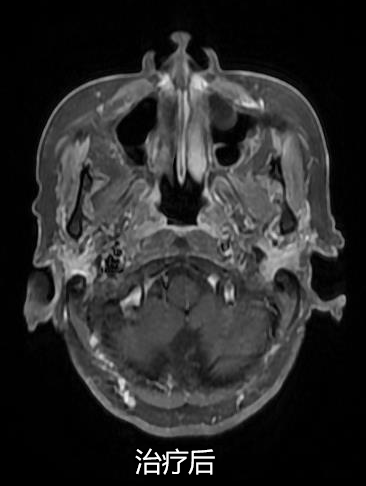

放射治療聯(lián)合免疫治療(肺癌伴腦轉(zhuǎn)移)